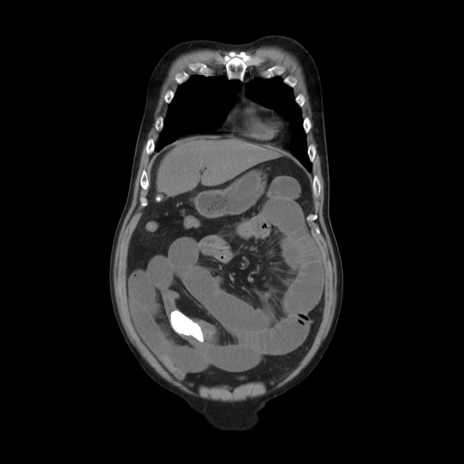

横断像